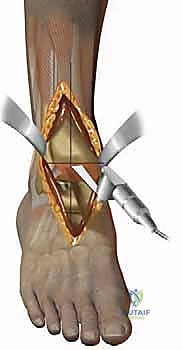

يتكون مفصل الكاحل الأساسي (المفصل الظنبوبي الكاحلي - Tibiotalar joint) من التقاء ثلاث عظام رئيسية:

1. عظمة الظنبوب (Tibia): وهي عظمة الساق الكبرى، وتشكل السقف والجزء الداخلي من الكاحل (الكعب الداخلي - Medial Malleolus).

2. عظمة الشظية (Fibula): وهي عظمة الساق الصغرى، وتشكل الجزء الخارجي من الكاحل (الكعب الخارجي - Lateral Malleolus).

3. عظمة الكاحل (Talus): وهي العظمة السفلية التي تستقر داخل التجويف الذي تشكله عظمتا الساق، وتعمل كنقطة ارتكاز محورية للقدم.

تُغطى نهايات هذه العظام بطبقة ناعمة ومرنة تسمى "الغضروف المفصلي" (Articular Cartilage). هذا الغضروف يعمل كوسادة ممتصة للصدمات ويسمح للعظام بالانزلاق فوق بعضها البعض باحتكاك يكاد يكون معدوماً. علاوة على ذلك، يُفرز المفصل سائلاً زلالياً (Synovial Fluid) يعمل كزيت تشحيم لضمان نعومة الحركة. عندما يتضرر هذا الغضروف لأي سبب، تبدأ العظام بالاحتكاك المباشر، مما يسبب الألم الشديد، التورم، وفقدان القدرة على الحركة؛ وهنا تبرز الحاجة الماسة للتدخل الطبي.